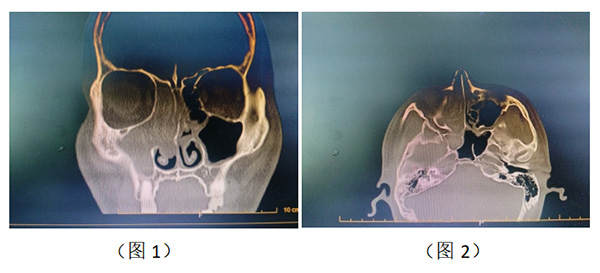

近日,我院耳鼻咽喉头颈外科为一名复发全组真菌性鼻窦炎患者实施鼻内镜下右侧全组鼻窦开放+窦内病变清除术,患者5年前因鼻塞症状于河北医科大学附属医院行"鼻内镜下右侧鼻窦开放术+鼻息肉切除术",术后症状缓解。3年前再次出现右侧鼻塞,就诊于当地医院,给予鼻喷药物,症状无缓解。1周前就诊于我院,行鼻实CT检查示:右侧全组鼻窦及鼻腔内软组织密度影。(图1、2)